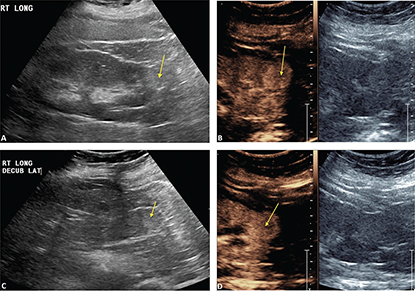

CEUS can be used to follow patients for residual or recurrent tumor with high accuracy. Any residual tumor will be identified as areas of increased enhancement. Absence of blood flow as in Figure 3B confirms complete ablation of the renal tumor. Note that it is not possible to determine if contrast is not utilized in Figure 3A. Figure 4 demonstrates a case where residual tumor (calipers) is present.

Figure 3. Successful ablation. Patient presented for 3-month post-RFA evaluation. (A) B-mode image before the ablation. Large heterogeneous tumor is noted on gray scale examination (arrow). (B) Absence of residual blood flow (arrow) is demonstrated on CEUS examination.

Figure 4. Tumor recurrence/inadequate ablation. Patient presented for CEUS examination 6 weeks after RFA. (A) The B-mode image demonstrates a complex mass (arrow) with solid and cystic components. It is not possible to determine if there is residual tumor. (B) CEUS image demonstrates the tumor (calipers) with residual flow in the posterior part of the tumor (arrow).